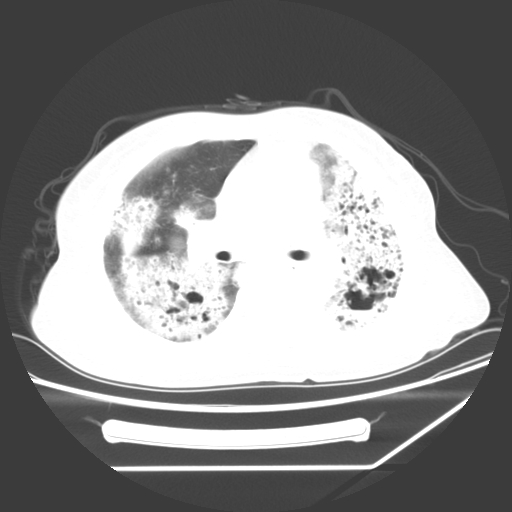

标题: CT25393:病人45岁,咳嗽,吐黄痰带血丝,发热,胸闷月余 [打印本页]

标题: CT25393:病人45岁,咳嗽,吐黄痰带血丝,发热,胸闷月余

1、左肺中央型肺癌并双肺弥漫性转移   2、双肺部感染    3、肺大泡     4、左侧胸腔积液

双侧肺弥漫性病变,可见“空泡征”及“蜂窝征”,考虑肺泡癌可能性大,左侧胸腔积液,考虑胸膜受累可能!

考虑肺泡癌,建议排除感染。

考虑肺泡癌

1)不排除肺泡癌可能。2)左侧胸腔积液。